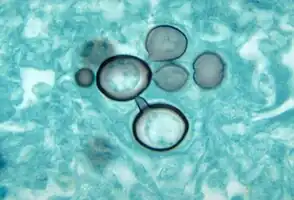

More than 90% of cases can be diagnoses with direct histological examination of tissue, such as sputum, bronchial lavage fluid, exudates and biopsies. Histopathological study with Gomori methenamine silver (GMS) stain or hematoxylin and eosin (H&E) stain revealing large yeast cells with translucent cell walls with multiple buds.[14]

Paracoccidioides histopathology

Paracoccidioides histopathology -

A culture of Paracoccidioides brasiliensis during its yeast phase

A culture of Paracoccidioides brasiliensis during its yeast phase -

Histopathology of paracoccidiodomycoisis

Histopathology of paracoccidiodomycoisis -